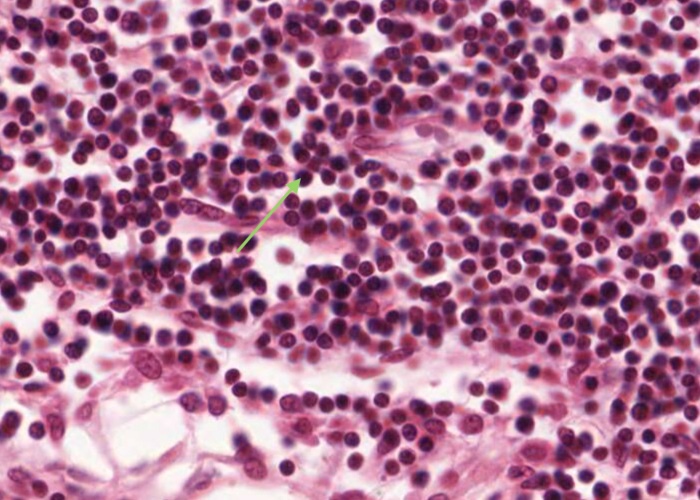

Finally there are substantial numbers of small lymphocytes each with a circular, dark-stained nucleus.